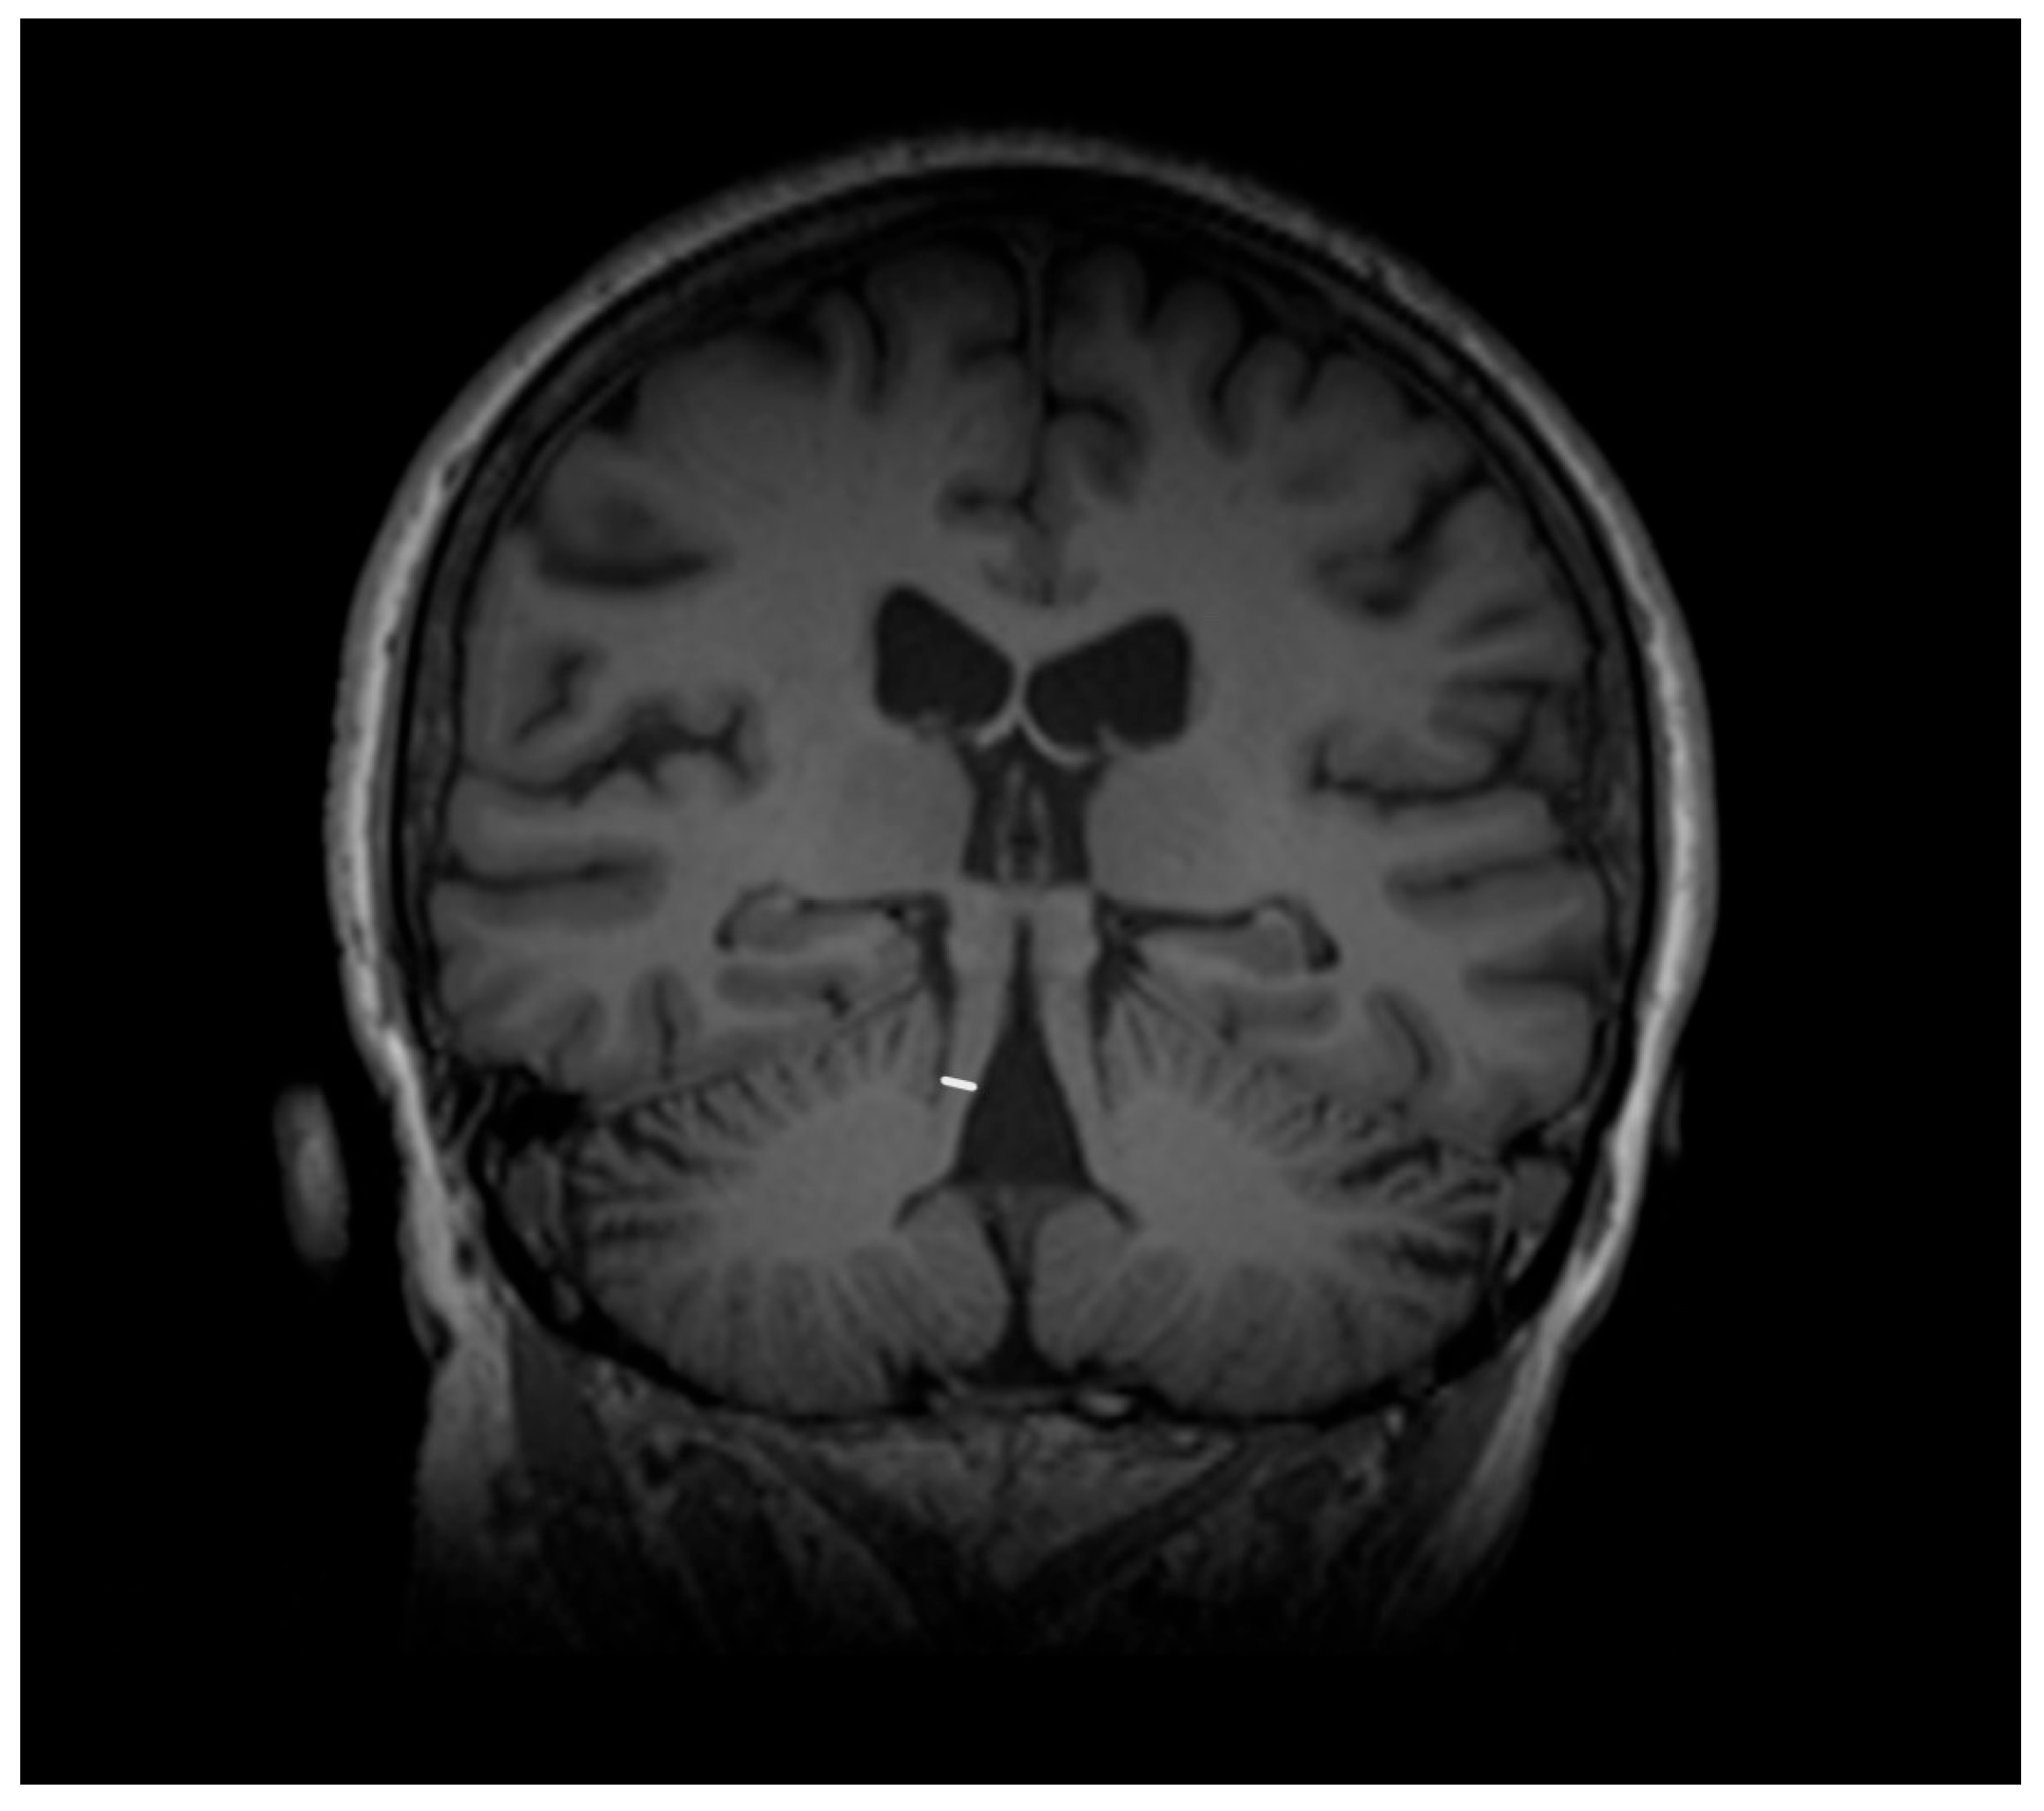

- Lenka, A.; Pasha, S.A.; Mangalore, S.; George, L.; Jhunjhunwala, K.R.; Bagepally, B.S.; Naduthota, R.M.; Saini, J.; Yadav, R.; Pal, P.K. Role of Corpus Callosum Volumetry in Differentiating the Subtypes of Progressive Supranuclear Palsy and Early Parkinson’s Disease. Mov. Disord. Clin. Pract. 2017, 4, 552–558. [Google Scholar] [CrossRef]

- Bianco, M.G.; Cristiani, C.M.; Scaramuzzino, L.; Sarica, A.; Augimeri, A.; Chimento, I.; Buonocore, J.; Parrotta, E.I.; Quattrone, A.; Cuda, G.; et al. Combined blood Neurofilament light chain and third ventricle width to differentiate Progressive Supranuclear Palsy from Parkinson’s Disease: A machine learning study. Parkinsonism Relat. Disord. 2024, 123, 106978. [Google Scholar] [CrossRef] [PubMed]